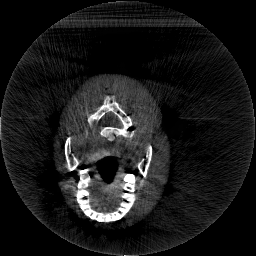

Krylov subspace methods are a powerful family of iterative solvers for linear systems of equations, which are commonly used for inverse problems due to their intrinsic regularization properties. Moreover, these methods are naturally suited to solve large-scale problems, as they only require matrix-vector products with the system matrix (and its adjoint) to compute approximate solutions, and they display a very fast convergence. Even if this class of methods has been widely researched and studied in the numerical linear algebra community, its use in applied medical physics and applied engineering is still very limited. e.g. in realistic large-scale Computed Tomography (CT) problems, and more specifically in Cone Beam CT (CBCT). This work attempts to breach this gap by providing a general framework for the most relevant Krylov subspace methods applied to 3D CT problems, including the most well-known Krylov solvers for non-square systems (CGLS, LSQR, LSMR), possibly in combination with Tikhonov regularization, and methods that incorporate total variation (TV) regularization. This is provided within an open source framework: the Tomographic Iterative GPU-based Reconstruction (TIGRE) toolbox, with the idea of promoting accessibility and reproducibility of the results for the algorithms presented. Finally, numerical results in synthetic and real-world 3D CT applications (medical CBCT and {\mu}-CT datasets) are provided to showcase and compare the different Krylov subspace methods presented in the paper, as well as their suitability for different kinds of problems.